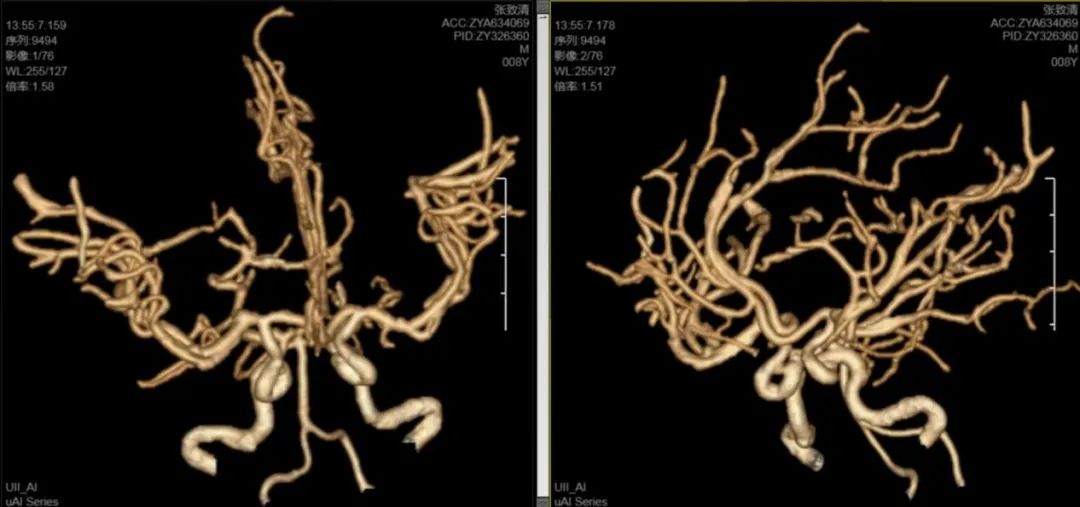

神经外科医疗中心吴鹏副院长解释道:小儿脑出血在临床上较为复杂,常见原因包括脑血管畸形、动脉瘤、血液系统疾病等,其中脑血管畸形最常见,处理较为复杂,手术风险极高。为进一步明确病因,排除脑血管畸形、动脉瘤等可能,立即为患儿进行了头颅CTA检查,结果未发现明显异常。

东方总院神经外科医疗中心张德辉院长和吴全主任对该患儿的病情高度重视,术前组织了详细的病例讨论,制定了周全的手术方案。由于出血部位靠近功能区,术后存在偏瘫风险;尽管CTA未发现异常,但仍不能完全排除颅内动脉瘤、脑血管畸形等病因,手术风险较高;手术将采用显微镜下精细操作,以预防可能的动脉瘤破裂或血管畸形出血,并减少手术创伤;同时,考虑到患儿年龄小,头部切口护理难度大,颅骨缺损不利于儿童身心康复,张德辉院长决定采取颅骨骨瓣回纳的方式,减少二次手术创伤。